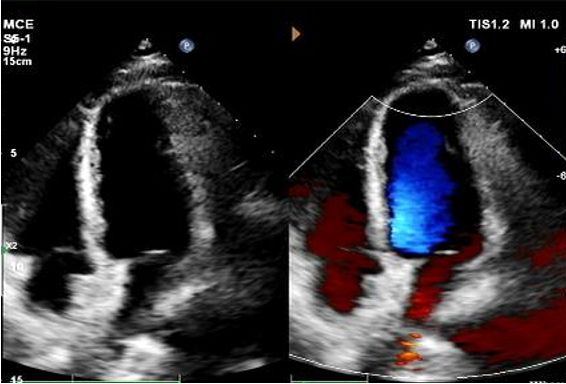

Today, we share a remarkable case highlighting 1-year post-op outcomes of MemoSorb in treating a complex long-tunnel PFO (12mm length, 1.4mm width), with a focus on serial echocardiographic evidence of device degradation and clinical symptom resolution.

No visible disc structures – replaced by 8mm tissue thickening at the septal implant site.

Zero residual shunt (rest or post-Valsalva).

Assorbimento completo del dispositivo confermato.